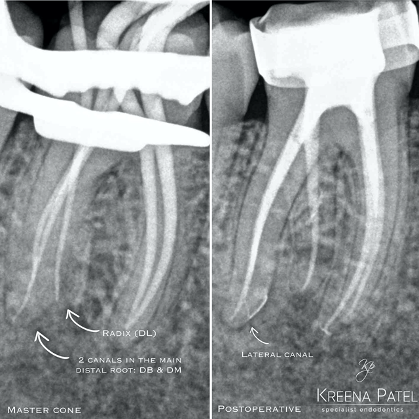

Three-dimensional imaging using CBCT is also very useful in identifying an additional root and treatment planning. It provides a ‘roadmap’ for endodontic treatment and highlights any curvatures present (Figure 5).

In a radix entomolaris, the main distal root (DB) may still have two canals (DB1 & DB2) (Figure 5). The DB2 is more difficult to locate and can be hidden in the isthmus between DB1 and DL. It is often in close proximity to DB1.

Use fine ultrasonics to conservatively open the isthmus to search for this canal (Figure 7).